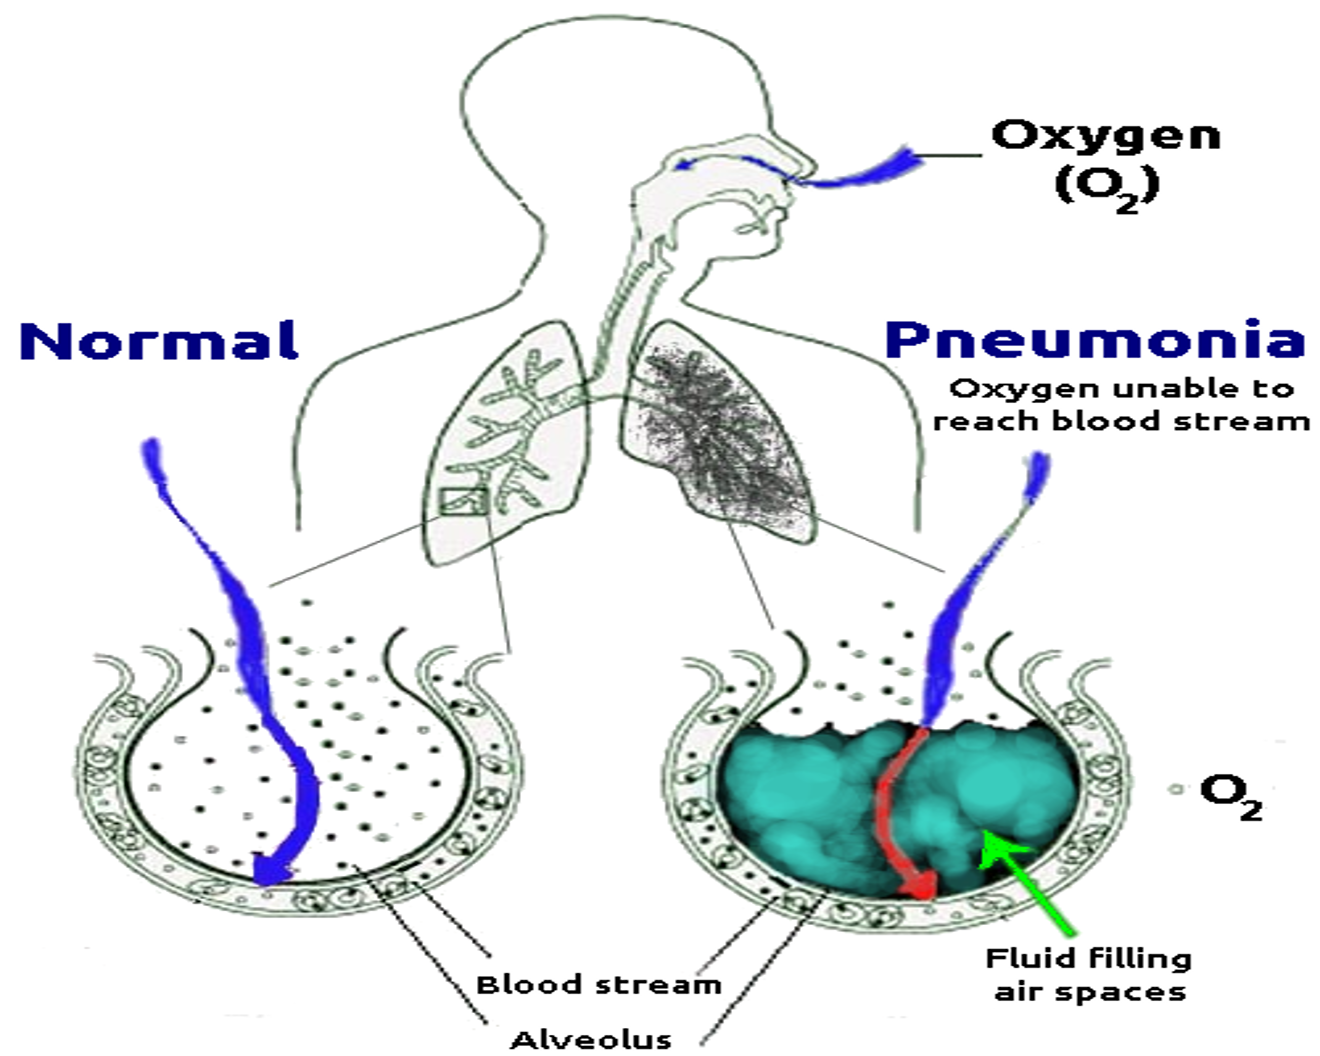

Pathophysiology

- Bacteria enter the lungs (from the throat or nose, airborne droplets, or blood).

- Bacteria may invade the spaces between cells and between alveoli.

- The macrophages and neutrophils inactivate the bacteria. The neutrophils also release cytokines.

- This causes general activation of the immune system.

- Leading to fever, chills, and fatigue.

- The neutrophils, bacteria, and fluid fill the alveoli.

- Resulting in the consolidation seen on chest X-ray.